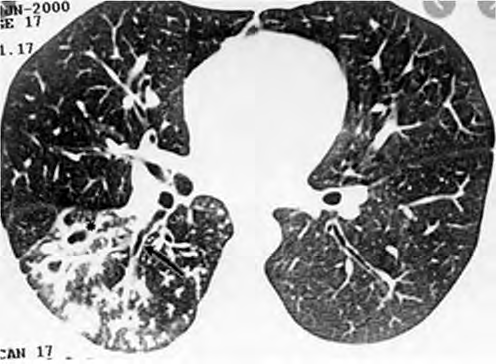

Um adolescente de 17 anos de idade procura atendimento em função de tosse vespertina, febre e hemoptise em pequena quantidade. Refere sudorese noturna e perda de peso. A tomografia de tórax apresenta nódulos centrolobulares com padrão de árvore em brotamento, além de pequenas cavitações espessas e de paredes irregulares, bem como brônquios espessados em segmento posterior do lobo inferior direito, conforme a imagem a seguir.

Acervo Pessoal.

Tendo em vista esse caso clínico, a imagem apresentada e os conhecimentos médicos correlatos, julgue os itens a seguir.